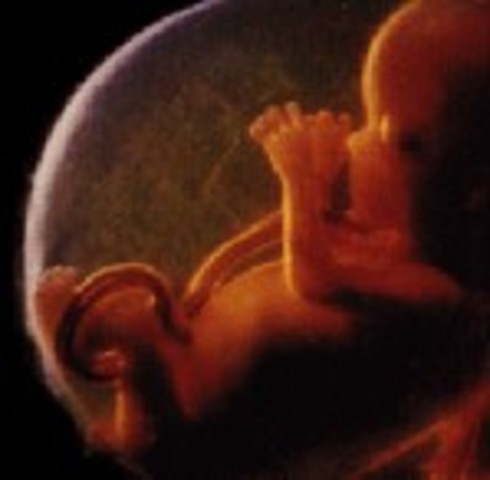

• week 10

week 10

Its now a fetus. muscles are being developed.